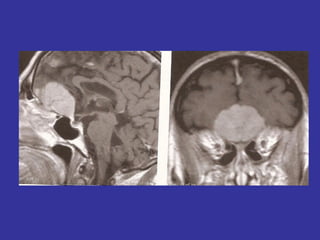

Nervo trigêmeo (V par)

V – NERVO TRIGÊMEO

• Misto

• 3 ramos (n. oftálmico, maxilar,

mandibular)

• Raiz sensitiva => gânglio de Gasser

(trigeminal, semilunar) => cavo

trigeminal - (parte petrosa do temporal)

• Sensibilidade da cabeça=>impulsos

exteroceptivos e proprioceptivos